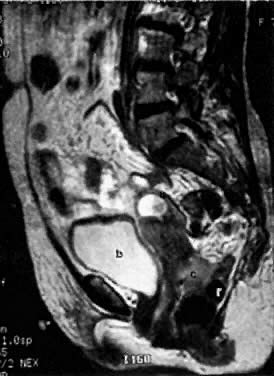

On T2-weighted magnetic resonance imaging (MRI), the normal cervix has two distinct zones (Fig. 1A, Fig. 1B, and Fig. 1C). The central 2- to 3-mm stripe of high signal intensity represents the epithelium and mucous glands in the cervical canal. This stripe is surrounded by a 3- to 8-mm zone of low signal intensity representing the fibromuscular stroma, which is continuous with the junctional zone of the uterus.2,3,4 A third peripheral, 2- to 8-mm zone of intermediate signal intensity is only seen in 15% of patients.2,3 The signal intensity of the cervix does not change with the menstrual cycle, but does change with pregnancy. As reported by Holland and associates,5 the predominant signal of the cervix is dark in the nonpregnant woman and in the first trimester, isointense in the second and third trimesters, bright at 72 hours before labor, and isointense postpartum. The parametria are depicted as two thin stripes of moderate signal intensity lateral to the cervix (Fig. 2A).6

Fig. 1. T2-weighted MRI of a normal female pelvis. A. Sagittal view of the uterine body, cervix, and vagina.

On MRI, uterine zonal anatomy is best depicted with T2-weighted imaging. Three distinct zones are seen (see Fig. 1A and Fig. 1B):

1. The central, high-signal-intensity zone represents the endometrium and its cavity. During the menstrual cycle, the width of this stripe ranges from 5 mm early in the cycle to 10 mm late in the cycle.44,45

2. The layer of low signal intensity that underlies the endometrium, called the junctional zone, corresponds to the inner layer of the myometrium. Its width does not vary during the menstrual cycle.

3. The peripheral intermediate-signal-intensity zone represents the outer portion of the myometrium. The latter varies in width and signal intensity during the menstrual cycle, reaching a maximum width of 25 mm and its highest signal intensity during the midsecretory stage.45,46 In postmenopausal women, both endometrium and myometrium decrease in thickness, with a consequent decrease in uterine size. At this stage, the endometrium should not exceed 5 mm in width.44,46